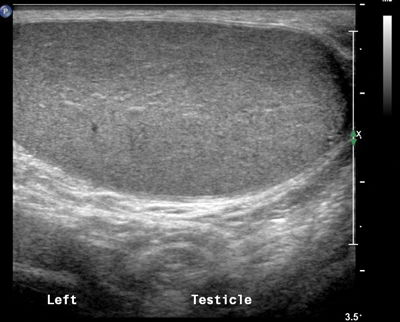

Figure 1: Longitudinal section through the left testis showing uniform echogenicity.

When performing testicular ultrasound, each testis should be examined individually to assess echogenicity and any focal lesion should be thoroughly examined to ascertain whether it appears benign or aggressive. The testis should be of uniform echogenicity as shown in Figure 1. Colour Doppler should be applied to ensure both testes have adequate vascularity. Any focal lesion should be assessed with colour Doppler to ascertain if a lesion is hypo- or hypervascular.